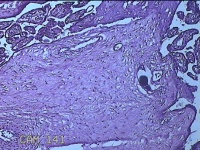

胎盘组织

性别

女

年龄

35岁

临床诊断

胎膜早破 早产

一般病史

停经36周,阴道流液3天。

标本名称

大体所见

灰白暗红色胎盘组织18x15.5x2.3㎝一个,表面光滑,血管清晰,颜色发暗,绒毛面结节状,轻度糜烂,表面有少许凝血块,切面见绒毛内有部分淤血,边缘蜕膜可见多个小血肿,脐带15x1.5x0.8㎝,切断脐带,见脐血管内有凝血块。